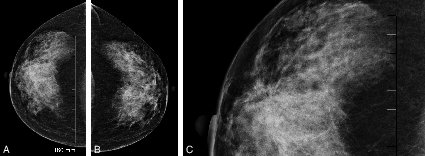

Figure 20.8. A, B, C Aspect de rupture architecturale à la mammographie

Figure 20.8. A, B, C Aspect de rupture architecturale à la mammographie.